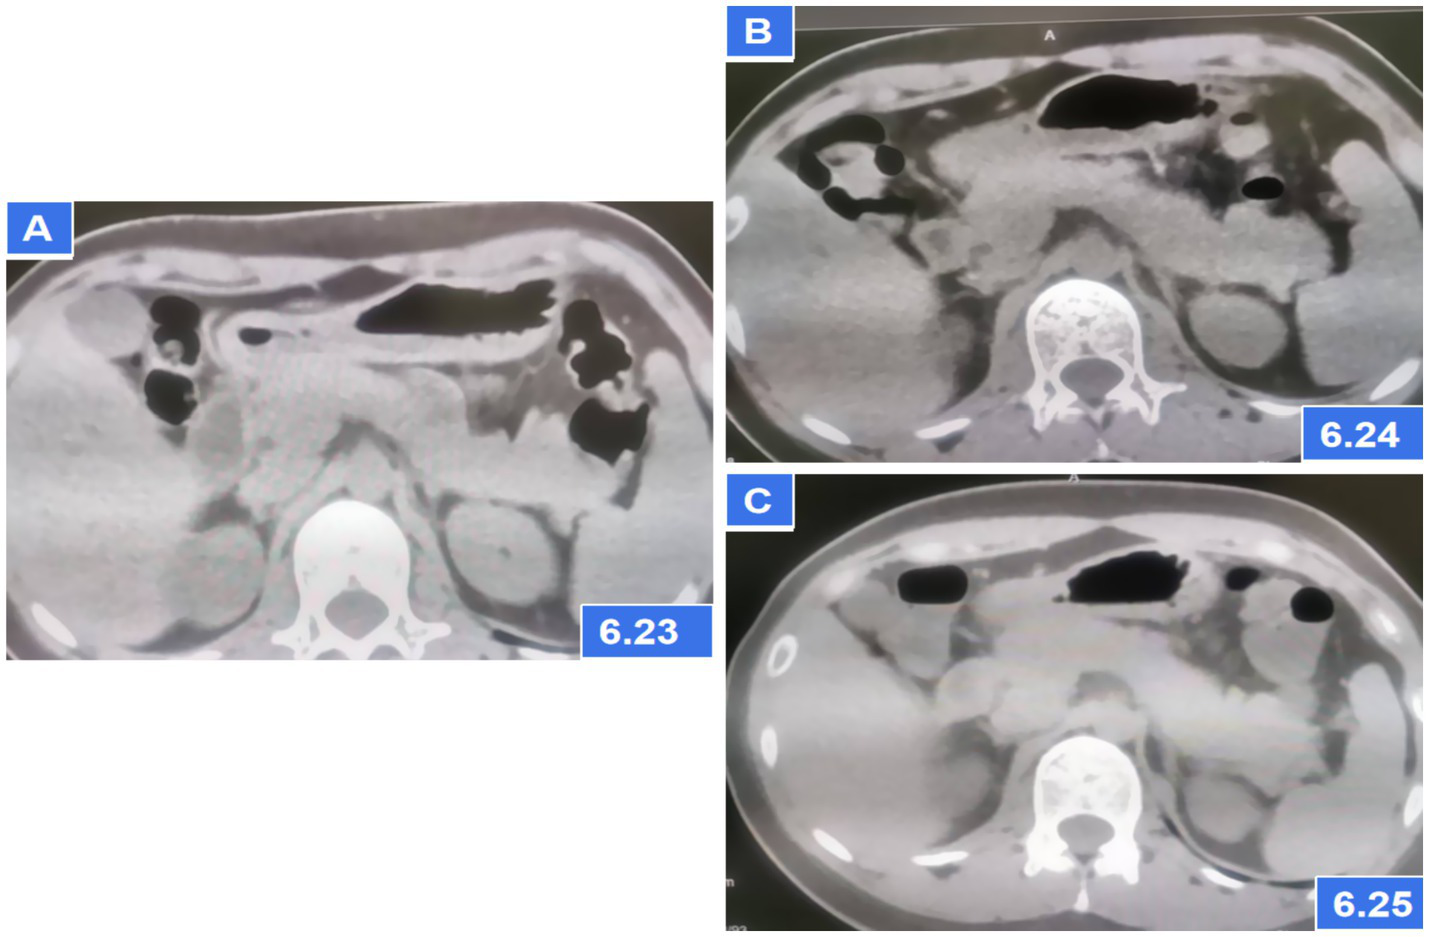

A 27-year-old female presented to the emergency department 3 h after ingesting 1,000 mg of sertraline (20*50 mg tablets). She had been prescribed sertraline 75 mg daily for depression diagnosed 1 month prior. The patient denied alcohol use, binge eating, biliary disease, or prior pancreatic/surgical interventions (e.g., endoscopic retrograde cholangiopancreatography). On examination, she was ambulatory, afebrile (37.2°C), with stable vital signs (pulse 92 bpm, respiratory rate 20/min, BP 118/83 mmHg). Abdominal examination revealed no tenderness, rebound, or guarding. Cardiac and pulmonary auscultation was unremarkable. Laboratory findings at admission included: Serum amylase: 228 U/L (reference: 30–110 U/L); Leukocytosis: 13.23 × 10 < sup > 9</sup>/L; Total bilirubin: 24.4 μmol/L; Arterial blood gas: pH 7.43, actual bicarbonate 19 mmol/L, carbon dioxide partial pressure 3.9 KPa, lactate 3.2 mmol/L. Other parameters (liver enzymes, electrolytes) were within normal limits. Admission CT: No pancreatic or biliary abnormalities (Figure 1A). Twelve hours post-admission, serum amylase rose to 684 U/L, while repeat CT demonstrated pancreatic edema without biliary obstruction or gallstones (Figure 1B). Urinary amylase remained negative (inconsistent with serum trends; assay-specific limitations noted), aligning with atypical DIP presentations where urinary markers may lag behind serum elevations.

Abdominal CT showing pancreatic parenchymal swelling; (A) CT scans on the first day after admission; (B) CT scans at 6 h later after admission; (C) CT scans after AP diagnosis and treatment for 2 days.

The patient met diagnostic criteria for AP per Chinese Guidelines (2021) (5) and Atlanta classification: (1) Serum amylase >3*upper limit; (2) Characteristic CT findings. Her BISAP score of 0 predicted mild disease. Management included: Gastric lavage (for overdose); fluid resuscitation (lactated Ringer’s: 250 mL/h), antibiotics (ceftriaxone), acid suppression and gastric mucosa protection (pantoprazole 40 mg IV BID); Supportive care (fasting). Monitoring: Serial amylase (down-trending to 241 U/L at 24 h) and repeat CT (normalization, Figure 1C). Sertraline was discontinued, and AP resolved without complications. On the third day of hospitalization (72 h), the patient had no complaints and requested discharge. Rechallenge with 50 mg sertraline during follow-up did not recur symptoms, suggesting dose-dependent toxicity. Combining the medical history and medication use, Per the China National Center for Adverse Drug Reaction Monitoring criteria (6), this case was graded as “probable” due to: Temporal association (onset ≤12 h post-overdose); Exclusion of alternative causes (biliary, alcohol, metabolic); Biochemical/histologic plausibility (SSRI-induced sphincter of Oddi dysfunction). Notably, rechallenge with sertraline 50 mg during follow-up did not recur, suggesting dose-dependent toxicity (Figures 2, 3).